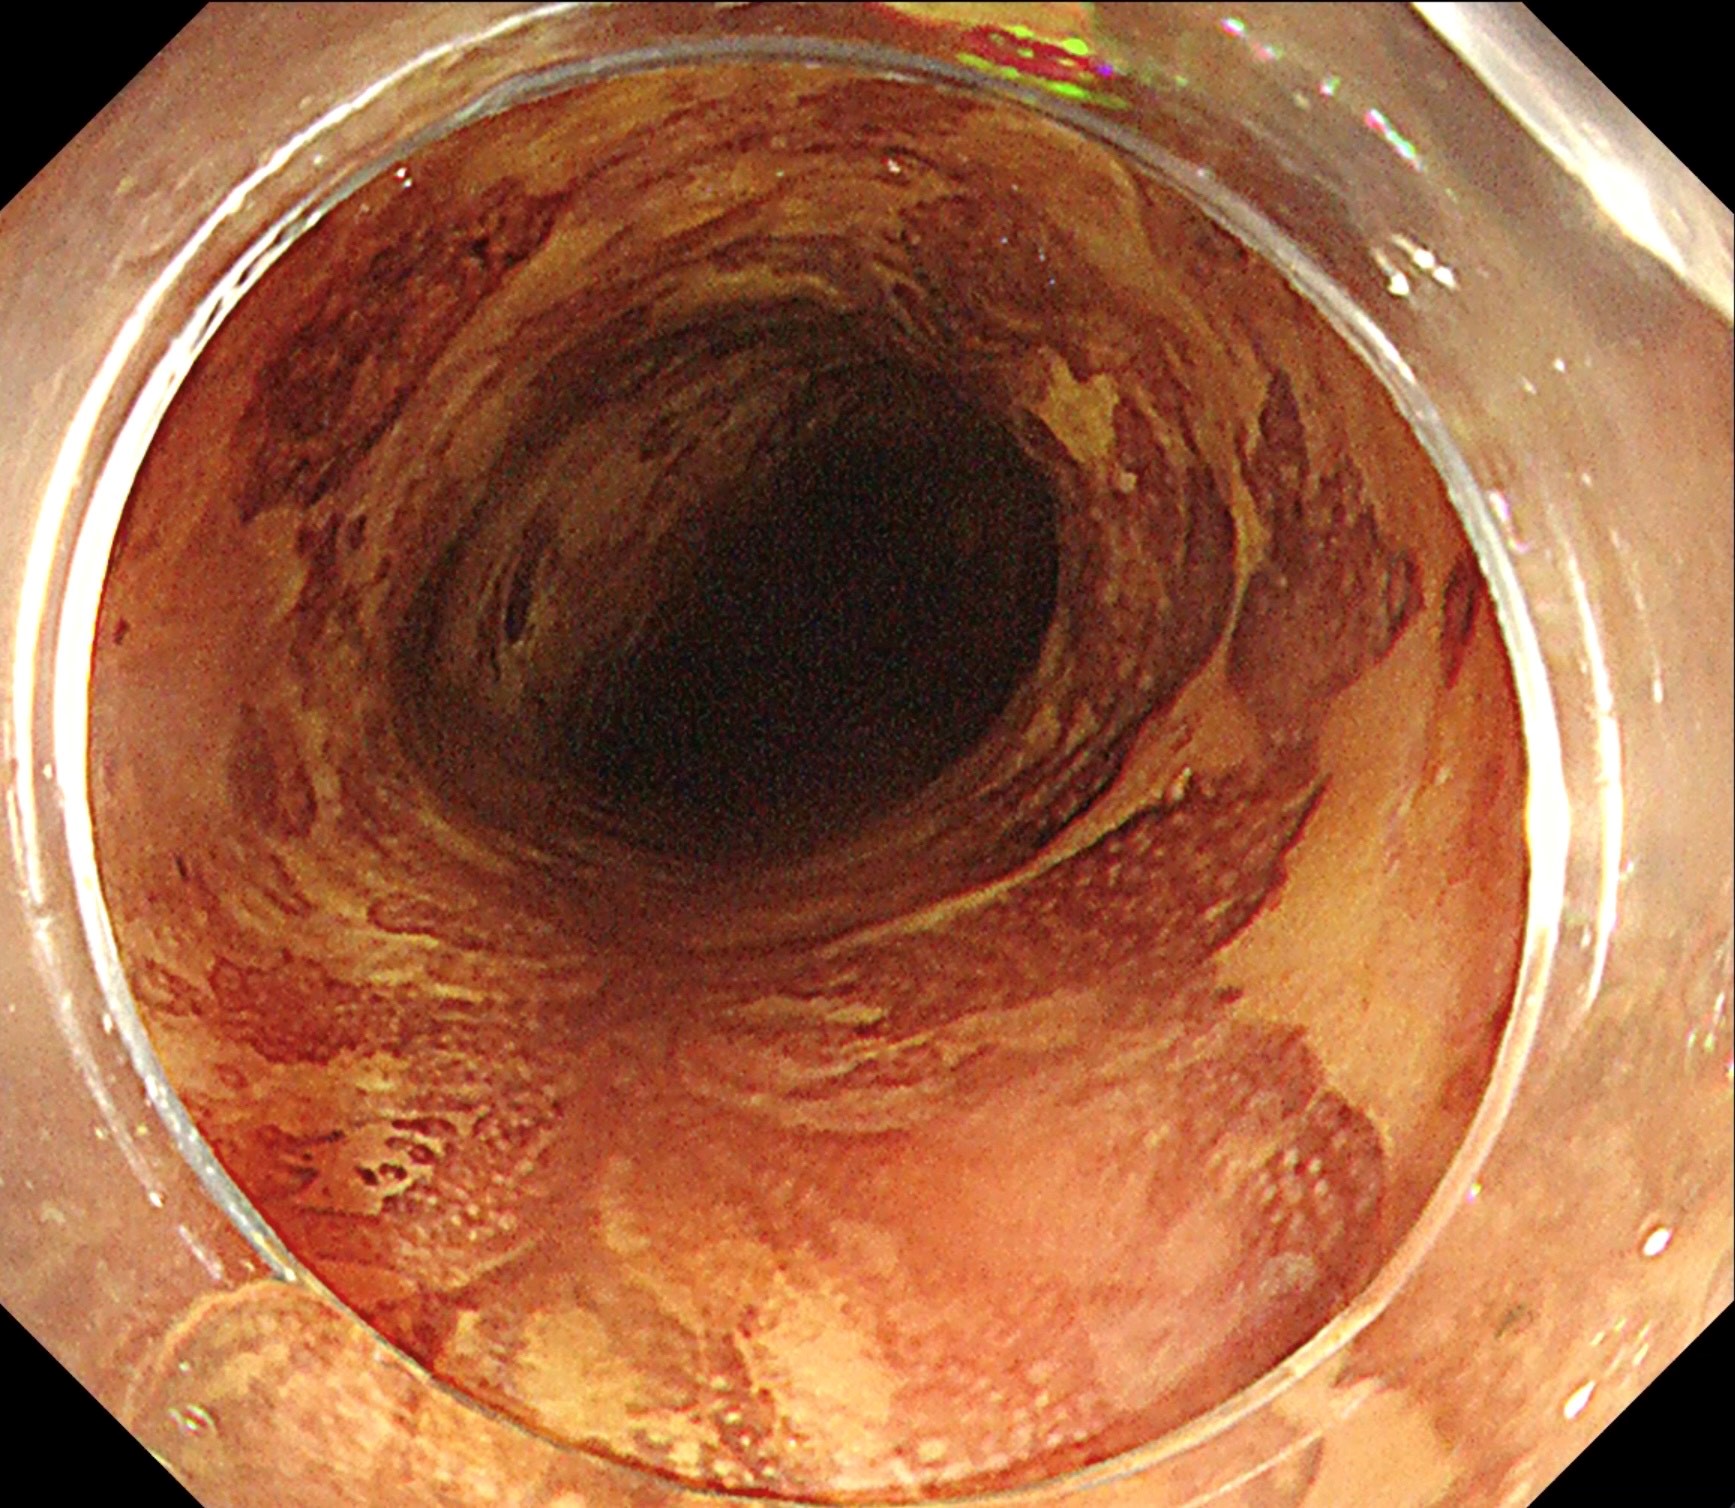

However, this added safety can decouple knife motion from dissection speed, tending to shallow the dissection layer (Fig. 3). Traction solves this completely. Clip-with-line traction stands the submucosa upright – like the adductor muscle of a scallop – enabling efficient, rapid dissection with the 3.5-mm blade while preserving the safety benefits of the ITknife nano tip and the safety of the “not excessively sharp” blade (Fig. 4).

Because of the colon’s curves and folds, unseen muscularis may lie in the knife path; pull-cutting can cause perforation, so it is usually avoided. Depending on scope position, pulling the ITknife from the five- or seven-o’clock channel can damage an unexpected fold, which understandably makes users hesitant. So why not dissect by pushing instead? As in the esophagus, the compact insulated tip allows the knife to crawl into the submucosa and dissect “from inside to outside”, i.e., toward the lumen, just like other knives – virtually eliminating perforation risk (Fig. 5). Efficient dissection with the blunt 3.5-mm blade and the ITknife nano safety profile is possible when the submucosa is kept upright with traction. Even in the transverse colon, where the effects of respiratory vibration are pronounced, or in the cecum, where the muscle runs perpendicular, the insulated tip makes perforation unlikely unless very strong force is applied. Lightly brushing the insulated tip on the muscle can actually stabilize the scope and shorten dissection time.